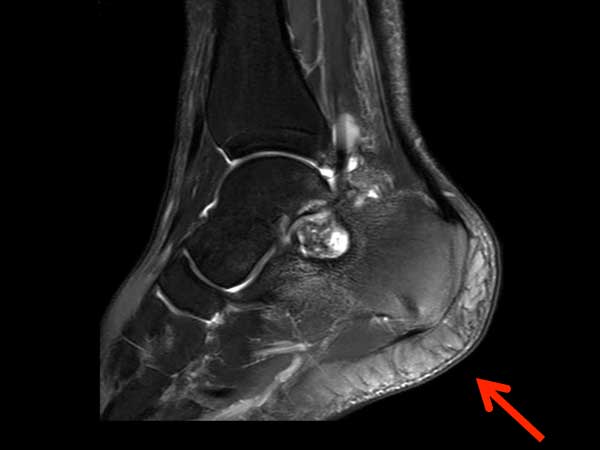

Sagittal T2w mDIXON